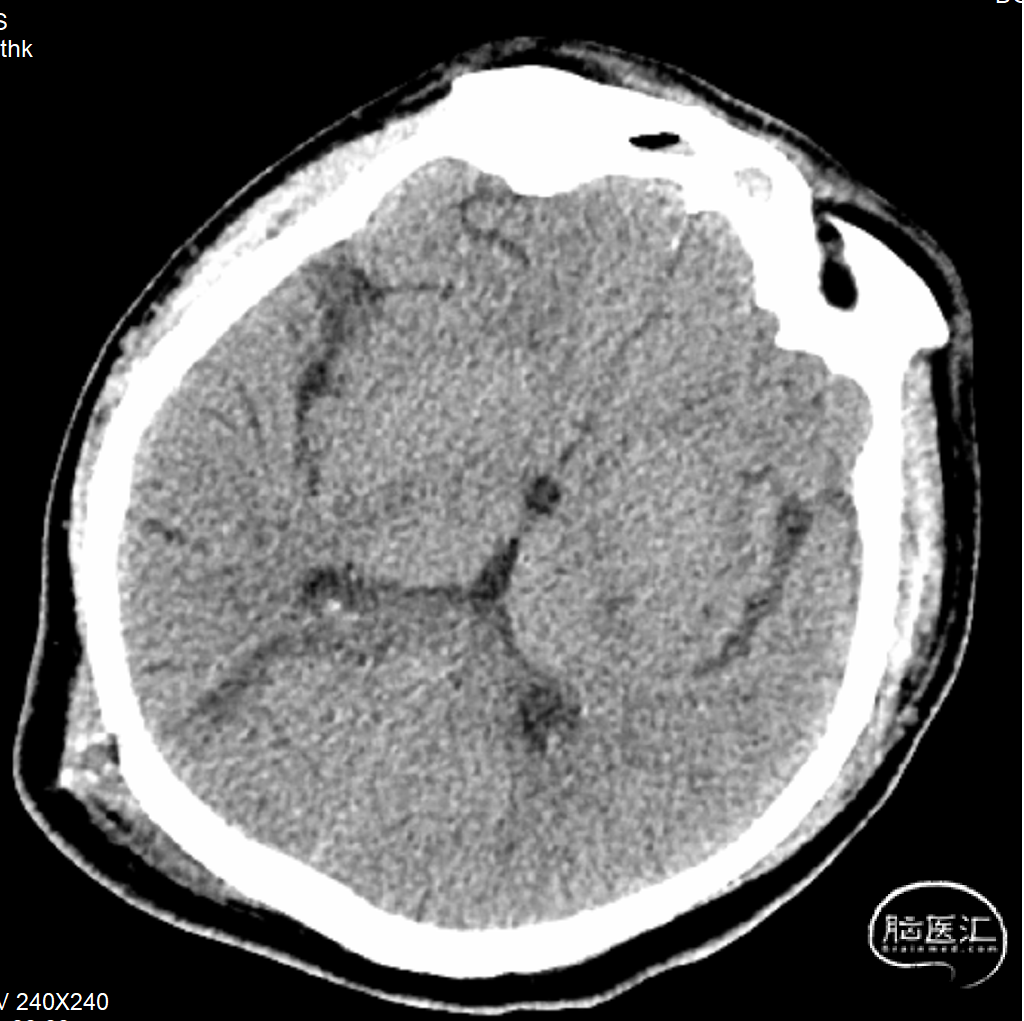

入院后完善头颅CT+CTA,头颅CT提示脑干血肿(图1)。CTA未见明确动脉瘤征象。